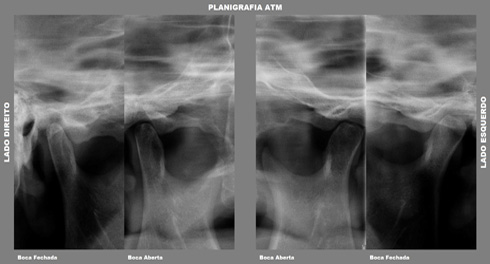

• Planigrafia de ATM

Tem a finalidade de melhor evidenciar o processo condilar em duas posições: abertura máxima (AM) e máxima interdigitação cuspidaria (MIC), em ambos os lados. É especifica para análise da estrutura condilar.